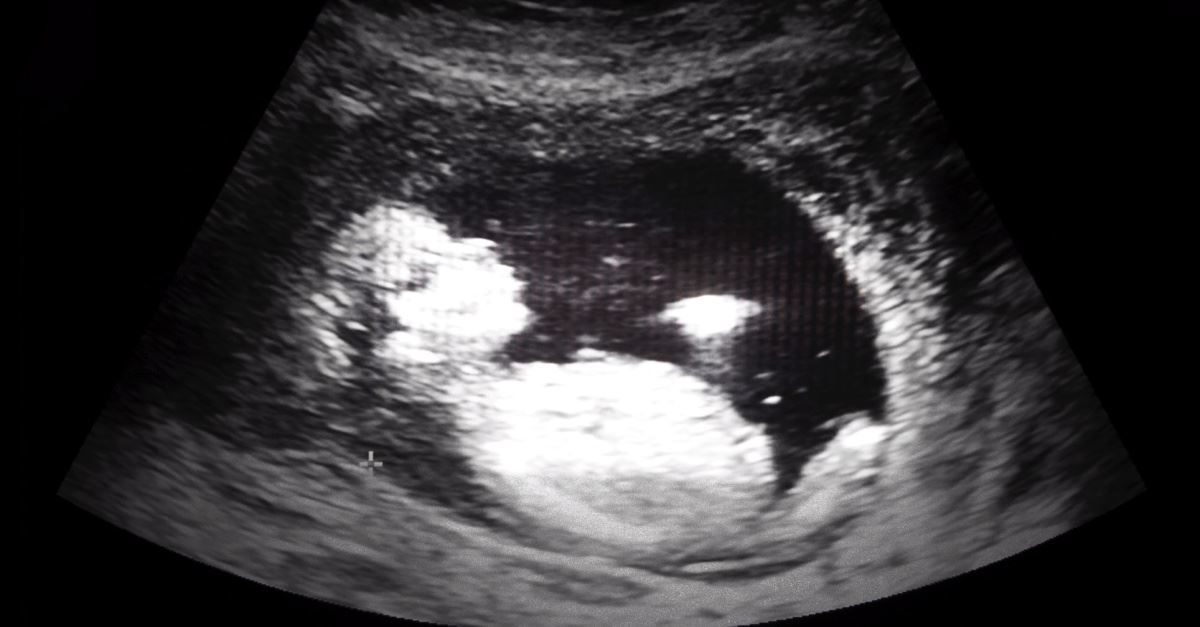

‘Babies Are Gross’: People Sign Petition to Protect Unborn Eagles, Refuse Petition to Protect Unborn Babies

LOS ANGELES -- In a video posted online on Wednesday, PragerU's Will Witt took to Echo Park in Los Angeles to ask the public to sign a petition to protect unborn eagles, followed by another petition seeking the protection